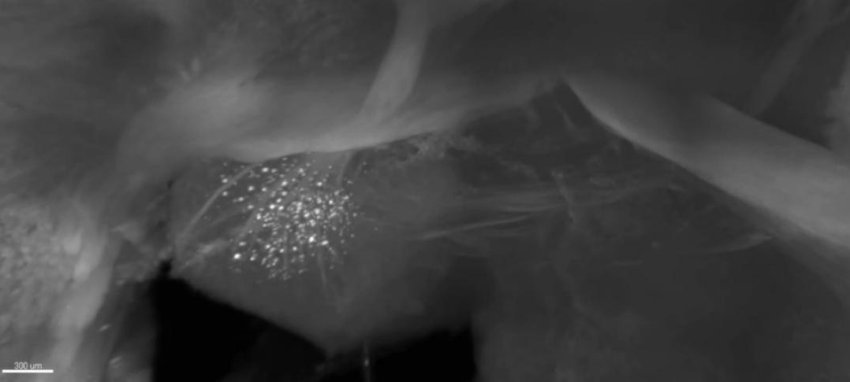

La marcia dell'amiloide nel topo di Alzheimer - A partire da un momento precoce della vita di un topo modello di Alzheimer (5XFAD), i ricercatori sono riusciti a vedere accumuli di placca amiloide (bianco) nelle prime fasi della malattia in regioni profonde del cervello. Nei mesi successivi, le placche si sono diffuse da lì lungo circuiti specifici. A ogni nuova età il video ricomincia dal corpo mammillare.

Il team ha utilizzato la SWITCH, una tecnologia sviluppata da Chung, per etichettare le placche amiloidi e illuminare l'intero cervello dei topi 5XFAD in modo che potessero essere visibili in dettaglio fine in età diverse. Il team è riuscito a vedere che le placche emergevano prima sempre nelle strutture cerebrali profonde e quindi le seguivano lungo i circuiti, come il circuito di memoria Papez, fin quando si erano diffuse in tutto il cervello a 6-12 mesi (la durata della vita di un topo è massimo 3 anni).